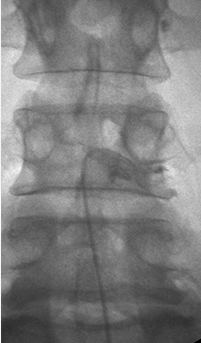

좁아진 신경 통로에 풍선 카테터를 넣어 공간을 넓히고 약물을 주입해,

다리 통증과 저림을 줄이는 최소침습 척추 시술입니다.

가느다란 카테터를 경막외 공간에 넣어 목(경추)·허리(요추) 신경 주변 유착과 염증을 풀어주고,

통증을 완화하는 최소침습 척추 시술입니다.